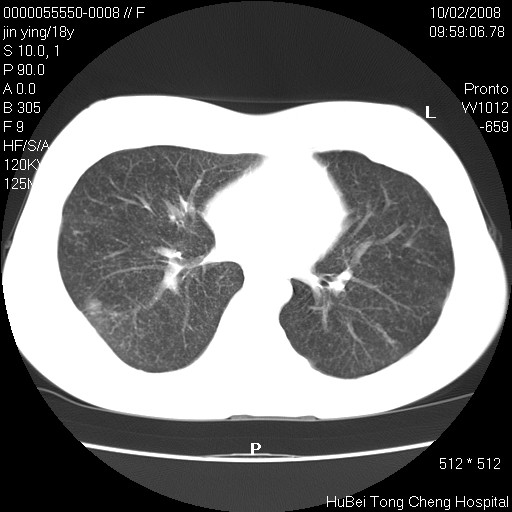

患者 女,18y。发热十余天,伴咳嗽。pe:t39⒈℃,bp 110/80mmhg,p 86次/min。神清,精神欠佳。双肺可闻及少许湿罗音。既往史不详。

临床诊断:肺部感染?

胸部ct轴位平扫(层厚10mm,螺距1.5,重建间隔10mm),图像如下: